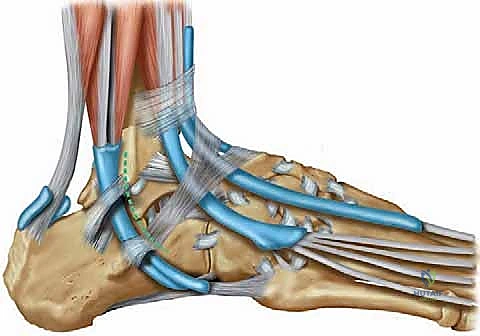

الخطوة 4: حفر الأنفاق العظمية (Bone Tunnels)

هذه هي المرحلة الأكثر دقة. باستخدام أدوات حفر دقيقة (Drill Guides) موجهة بالأشعة داخل غرفة العمليات، يقوم الدكتور هطيف بحفر أنفاق صغيرة جداً في المواقع التشريحية الدقيقة لمرتكزات الأربطة الأصلية:

* نفق في عظمة الشظية (Fibula).

* نفق في عظمة الكاحل (Talus) لتعويض رباط ATFL.

* نفق في عظمة الكعب (Calcaneus) لتعويض رباط CFL.

الخطوة 5: تمرير الوتر وتثبيته (Graft Passage & Fixation)

يتم تمرير وتر العضلة الأخمصية عبر هذه الأنفاق العظمية بطريقة هندسية تحاكي شكل الأربطة الطبيعية (غالباً على شكل حرف V أو Y). بعد تمرير الوتر، يتم ضبط درجة الشد بدقة متناهية؛ بحيث لا يكون الكاحل مشدوداً جداً (مما يعيق الحركة) ولا مرتخياً (مما يعيد عدم الاستقرار).

يتم تثبيت الوتر داخل الأنفاق العظمية باستخدام مسامير تداخلية قابلة للامتصاص (Bioabsorbable Interference Screws) أو خطاطيف معدنية دقيقة (Suture Anchors). هذه المواد توفر تثبيتاً فورياً وقوياً يسمح ببدء التأهيل المبكر.